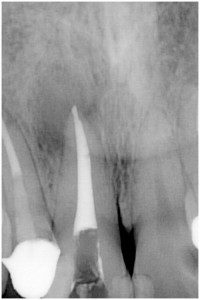

歯髄壊死 左下の小臼歯 川口の歯科 歯医者 さかえ歯科クリニック

2014年12月16日

術 後

術 前